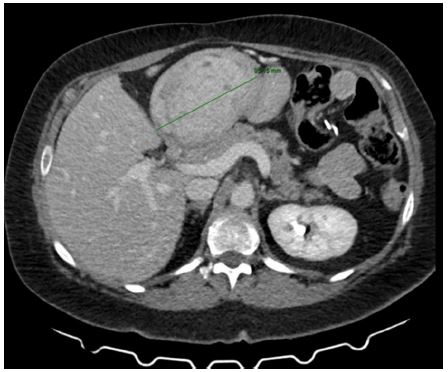

A 57-year-old woman with a history of hypertension, depressive syndrome, right hemithyroidectomy, and several bariatric procedures (Table 1) was hospitalized in the Internal Medical Unit of our clinic for an episode of acute anemia (hemoglobin 79 g/L). She had a well-known iron deficiency anemia that had been present for one year and was being treated with iron carboxymaltose. During the hospitalization, she received transfusions of packed red blood cells, and an Esophagogastroduodenoscopy (EGDS) was performed. It revealed a bulky, vegetant, ulcerated neoformation affecting the angulus/anterior wall of the stomach (Figure 1). The neoformation was sampled with biopsy forceps, and it was histologically defined as a superficially eroded hyperplastic polyp. The Helicobacter Pylori was negative on histological examination (Figure 1).

Figure 1: Endoscopic image of the neoformation affecting the angulus/anterior wall of the stomach.